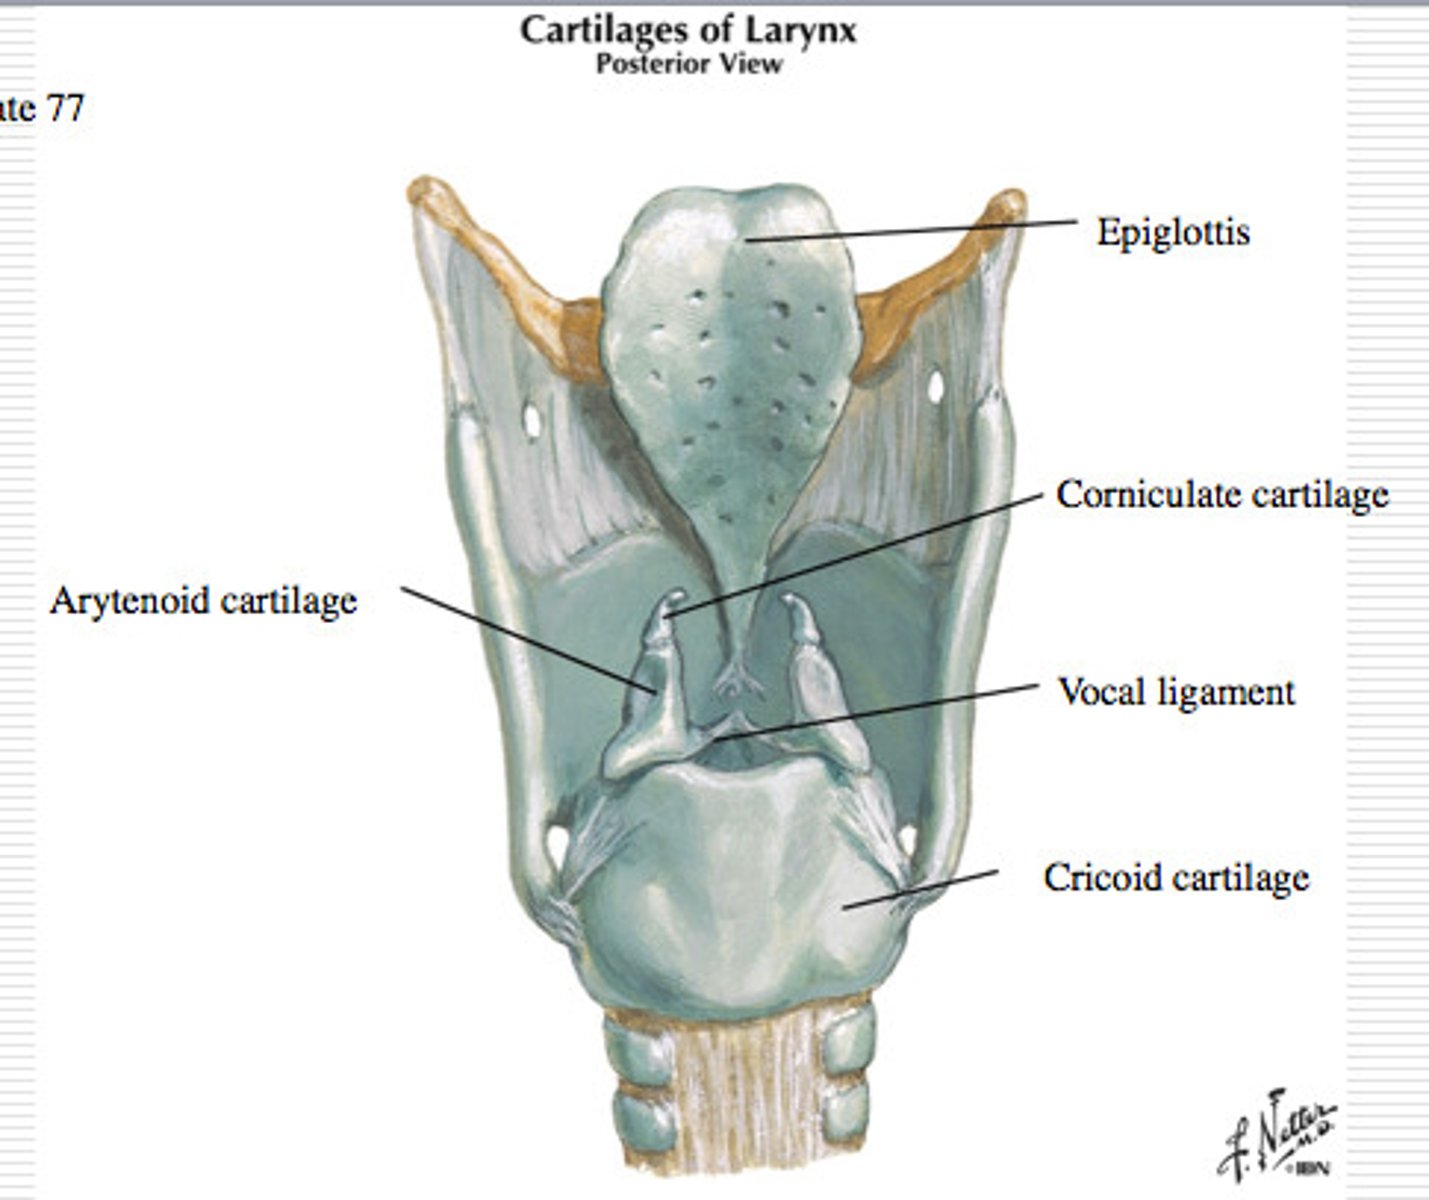

Larynx

Laryngeal Cartilages

Largely construct the larynx (voice box)

Cricoid Cartilage

The ring-shaped structure that forms the lower portion of the larynx

Vocal Folds

Mucosal folds that function in voice production (speech); also called the true vocal cords.

Epiglottis

A flap of cartilage at the root of the tongue, which is depressed during swallowing to cover the opening of the windpipe